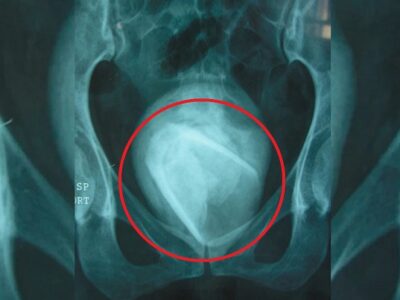

Врачи прооперировали ребенка, удалив большой нарост, но не стали больше ничего делать, сказав, что девочка должна сначала подрасти, чтобы стало ясно, что в целом следует сделать.

Сейчас Лакшими 6 лет и на ее лице по центру пролегает огромный шрам, который делит ее лицо на две части. У нее два носа, глаза находятся на большом расстоянии друг от друга, а рот такой широкой, словно это два рта в одном.

Неизвестно, какая именно аномалия у этой девочки, но ранее высказывались версии, что это редкая мутация при вынашивании близнецов.